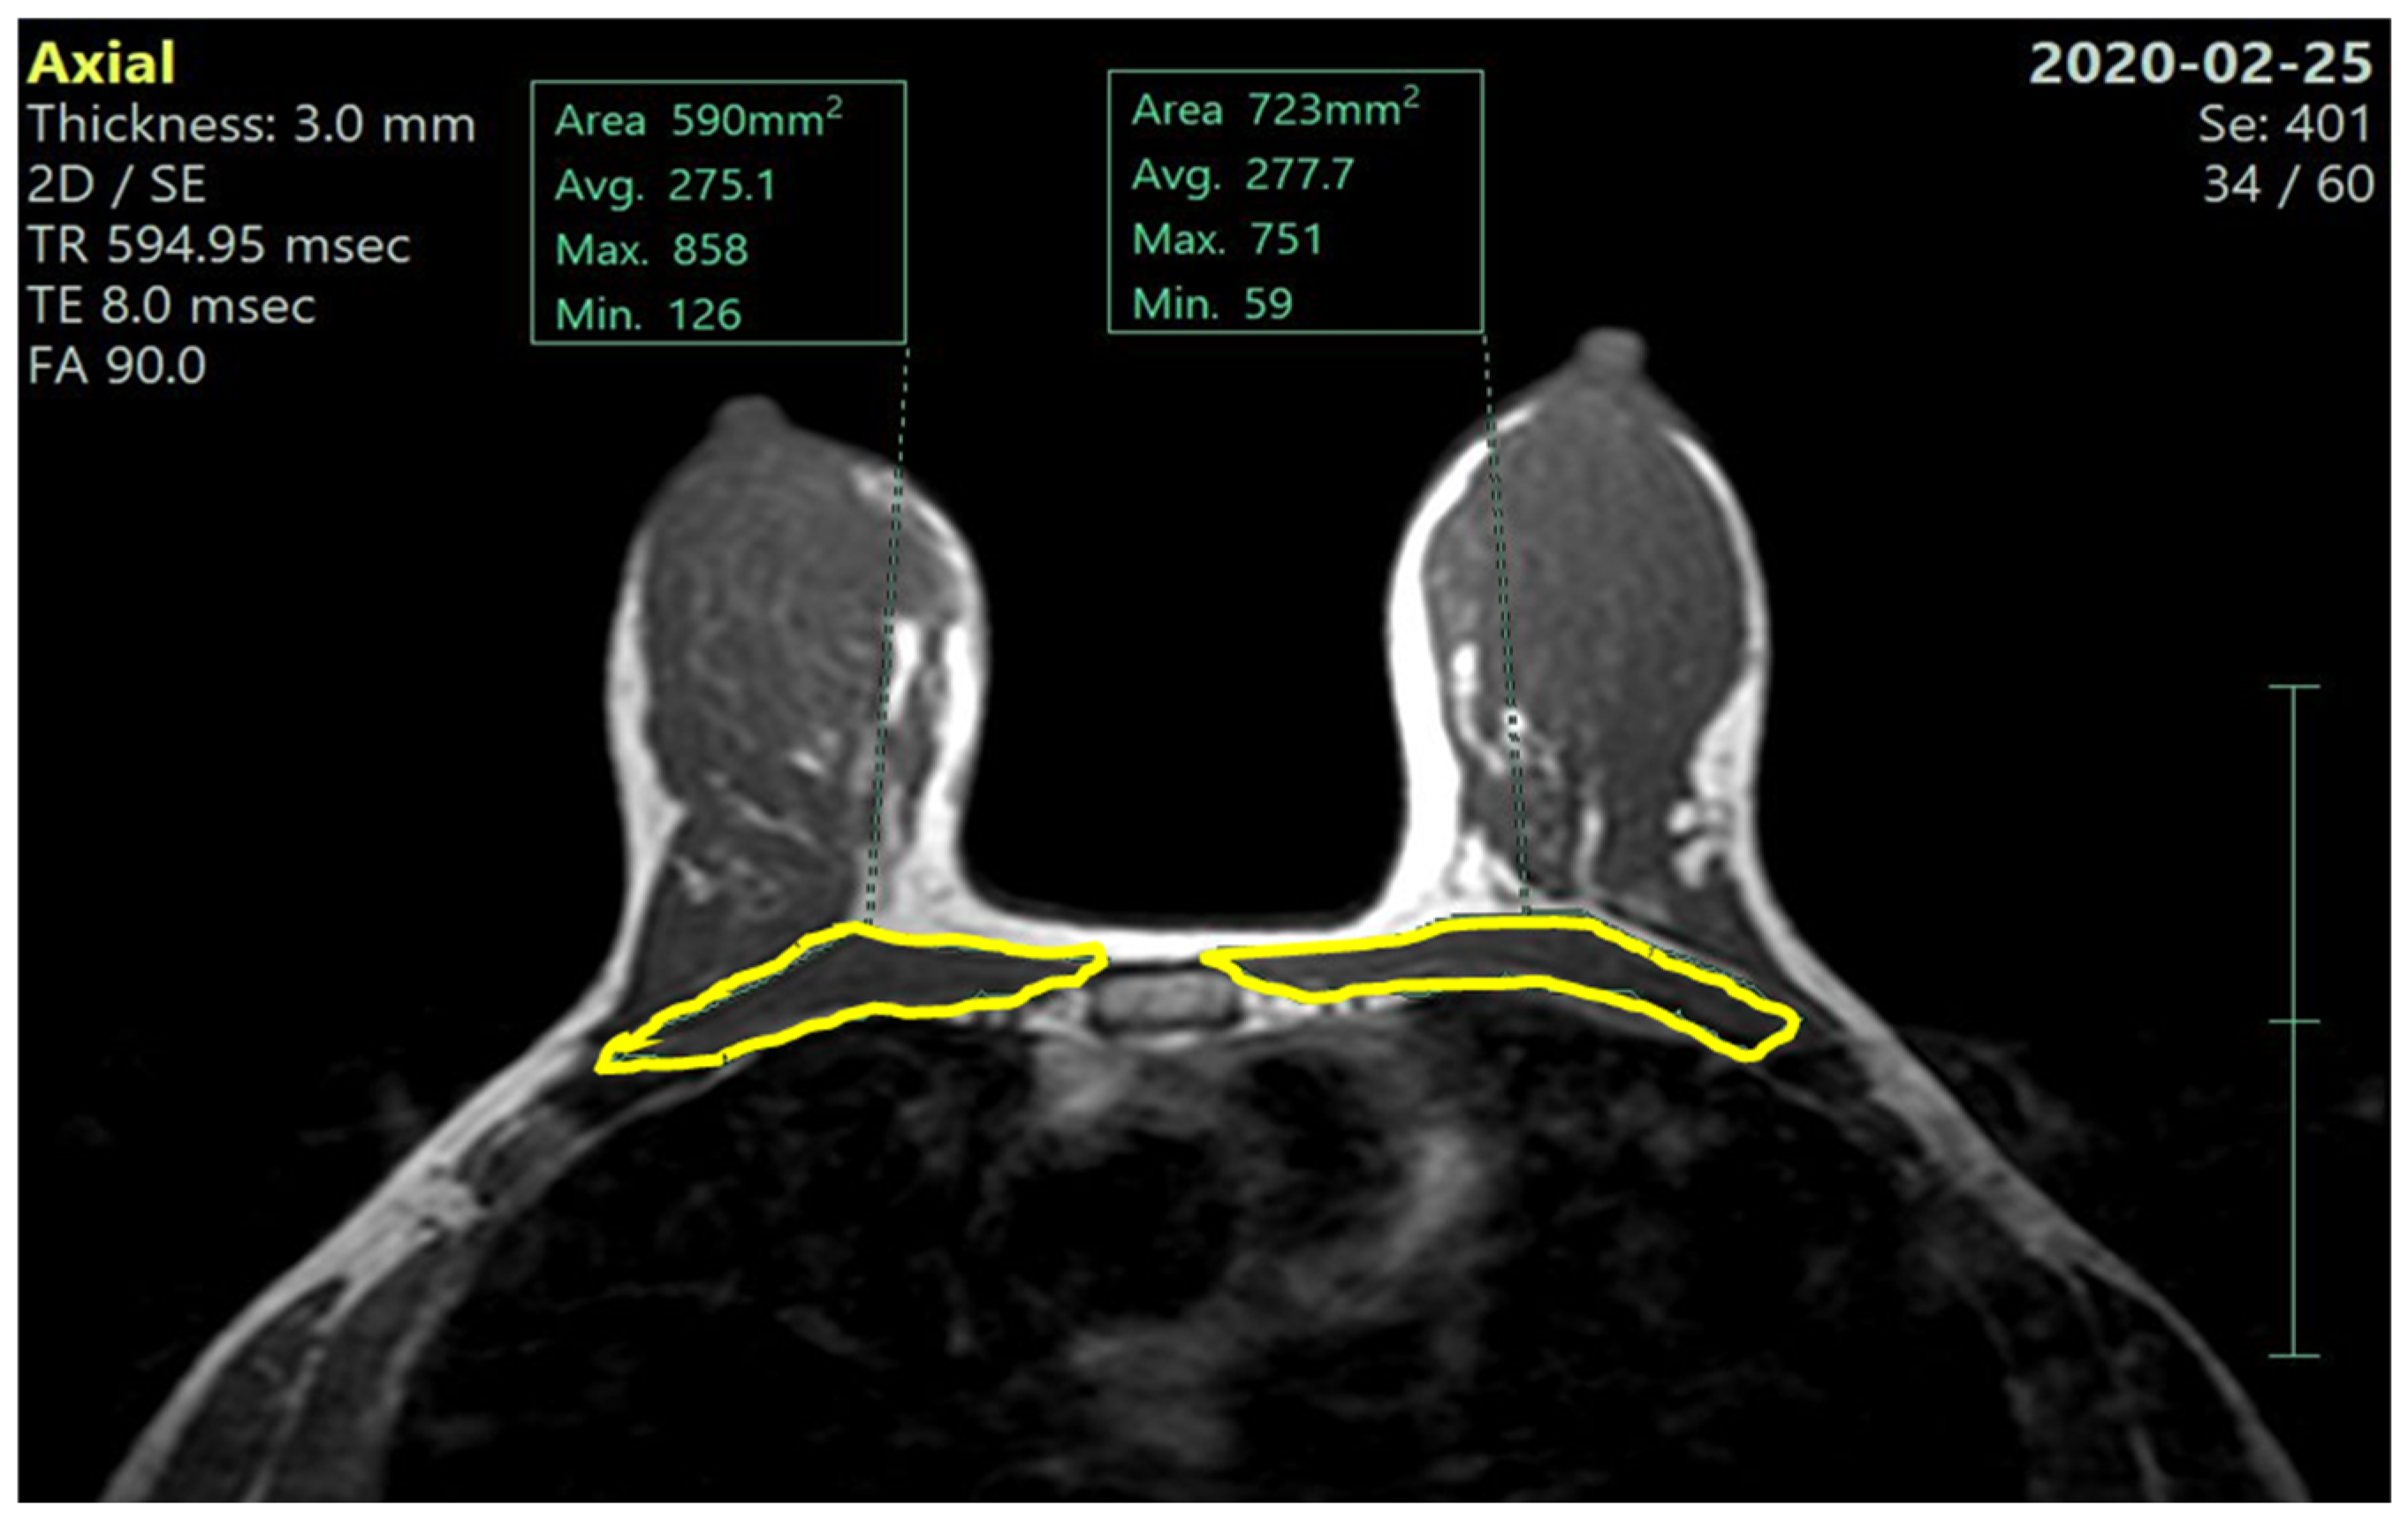

We measured, on both before- and after-NACT MRI scans, the whole pectoralis muscles area (PMA): we selected an axial image in the T1-weighted sequence at the level of the Louis angle (manubriosternal joint; second costal cartilage). On this reference image, using a dedicated software, we segmented the right and left pectoralis muscle along the muscle profile as shown in Figure 1 and Figure 2, automatically obtaining the pectoralis area, expressed in cm2.

Figure 1. Pre-NACT left and right pectoralis muscle areas (MRI—axial T1 non-fat sat image).